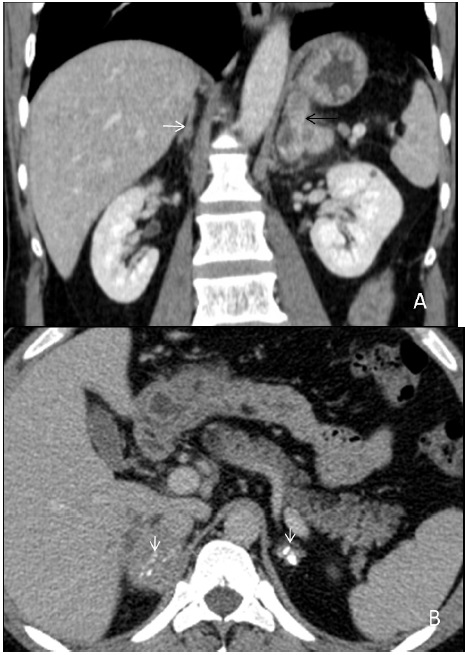

Hepatosplenic tuberculosis

Isolated hepatic or splenic involvement is rare in tubercular infection. It is almost every time associated with the lung or involvement of another abdominal organ. Mainly two broad types of features are there in hepatic or splenic tuberculosis, i.e. military or macronodular. The miliary type is associated with hematogenous dissemination, therefore involving the whole liver or spleen, resulting in liver/spleen enlargement and deranged liver functions. Whereas in macronodular type, dissemination is through a portal vein in which multiple hypodense lesions are observed scattered diffusely in the liver or spleen (Figure 7A). Calcification can also be seen in the chronic phase (Figure 7B). These macronodular presentations may confuse with abscess or metastasis. The involvement of the biliary tree by tuberculosis is even rarer, and its annual incidence is estimated to be 0.1%. If the biliary tree is involved, it is secondary to compression by hepatic granulomas. The gall bladder is rarely involved.

Figure 7: (A) A 40 years old male patient presented with pain abdomen and fever. The USG showed the presence of multiple hypoechoic lesions in the spleen, and a CECT abdomen was performed for further evaluation. The reformatted coronal image of the venous phase reveals hepatosplenomegaly and tubercular involvement of spleen in the form of innumerable tiny hypodense lesions diffusely scattered in splenic parenchyma (microabscesses) (white arrows). Liver biopsy was performed in the same patient due to persistent deranged liver function tests that demonstrated multiple caseating granulomas. Presently, the patient is on ATT and kept on follow-up every six weeks. (B) In another 60 year old male patient, who presented with cough and weight loss, non-contrast CT scan image in axial plane demonstrated calcified nodules involving splenic (black arrows) and hepatic parenchyma (white arrow) that signifies an old healed infection.